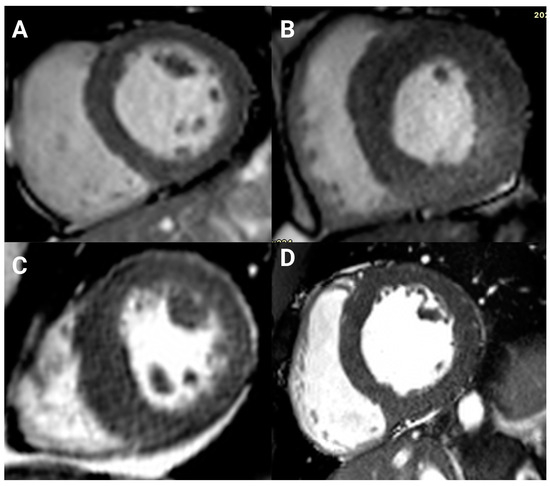

3.3. Late Gadolinium Enhancement

| LGE, n/contrast study, n (%) | 52/69 (75) | 8/18 (44) | 44/51 (86) | <0.001 |

| Ischemic pattern | 11/69 (16) | 0 (0) | 11/51 (22) | |

| Nonischemic pattern | 41/69 (59) | 8/18 (44) | 33/51 (65) |

| 41 (78.8) |

| Right ventricular insertion point | 13 (25) |

| Focal and right ventricular insertion point | 1 (1.9) |

| Mid wall and right ventricular insertion point | 17 (32.7) |

| Patchy mid wall | 7 (13.5) |

| Focal, mid wall, and right ventricular insertion point | 1 (1.9) |

| Subepicardial, mid wall, and right ventricular insertion point | 1 (1.9) |

| Subepicardial | 1 (1.9) |